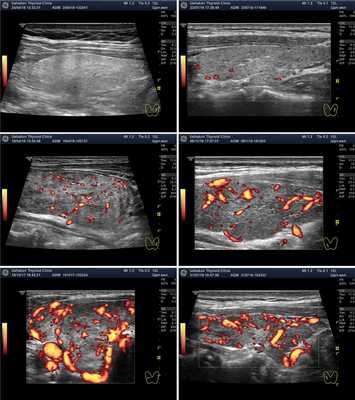

Рисунок 2. Два варианта ультразвукового допплеровского режима ― ЦДК (цветовое допплеровское картирование) и ЭДК (энергетическое допплеровское картирование). Программа УЗ-аппарата показывает сосуды цветом. Красным и синим при ЦДК и алым ― при ЭДК. При ЦДК видны сосуды (артерии и вены), несущие кровь в разных направлениях). При ЭДК не видно направления течения крови, но меньше погрешностей.

Рисунок 4. УЗИ ― допплеровское исследование интенсивности кровотока щитовидной железы. Показаны несколько вариантов: Ослабленный кровоток, нормальный кровоток, Малое усиление кровотока, Умеренное усиление кровотока и Значительное усиление кровотока.